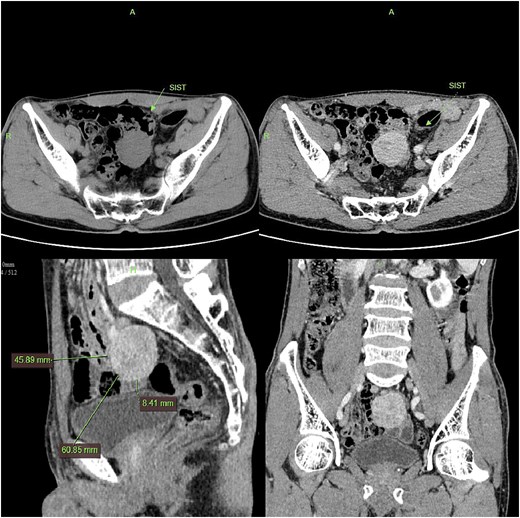

The patient underwent laparoscopic resection under general anesthesia in the lithotomy position. Intraoperative exploration identified a 4 cm ileal mass with significant omental adhesions, which were dissected using an ultrasonic scalpel. En bloc resection of the mass with adjacent ileal segment was performed. Histopathological examination confirmed a poorly differentiated GIST (Fig. 4).

Gross specimen photograph of the laparoscopically resected tumor (right panel) with corresponding histopathological sections (left panel).

Histopathological analysis remains the diagnostic gold standard for GIST. In this case, microscopic examination revealed spindle cell morphology. Immunohistochemical staining was positive for CD117 and DOG1, with a Ki-67 proliferation index of 3%. Findings were negative for SMA, Desmin, and S-100, confirming the diagnosis of GIST [4].